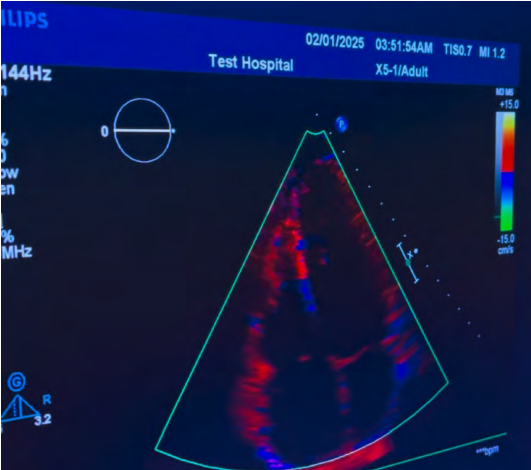

Ecocardiograma de estrés con Dobutamina

Es la evaluación funciona del corazón sometido a un incremento progresivo de la frecuencia cardíaca a través de un medicamento llamado Dobutamina, el cual se aplica en infusión por vía venosa. Su uso más común es para detectar obstrucciones en las arterias coronarias (las que nutren al tejido del corazón). Su presencia se denomina cardiopatía isquémica y se relaciona con angina de pecho, infarto y muerte súbita.